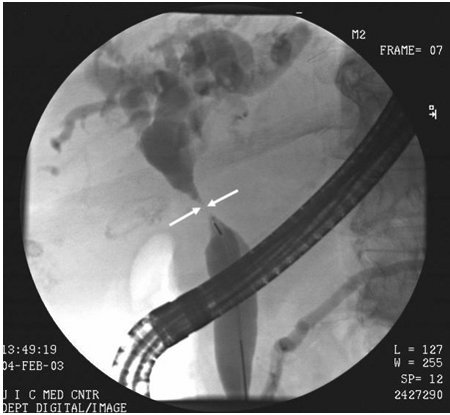

Cholangiocarcinoma

ERCP image of hepatic duct cholangiocarcinoma with duct stricture (arrows)

From the collection of Dr Joseph Espat; used with permission